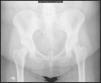

Las pruebas complementarias no siempre resultan útiles. La radiografía anteroposterior (AP) de la articulación confirma un característico espacio articular incrementado, aunque no siempre es definitiva ya que no es el método más adecuado por el riesgo de radiación sobre el feto (fig. 1). En ocasiones la presencia de quistes, cambios degenerativos u otras manifestaciones propias de otras patologías justificarían la etiología del cuadro clínico. La ecografía abdominal puede ayudar en el diagnóstico y monitorización del tratamiento, estableciendo la medida de la hendidura articular de manera inocua. La resonancia magnética nuclear, como prueba más específica, nos mostrará no sólo las estructuras óseas y sus cambios, sino también el estado de las partes blandas.